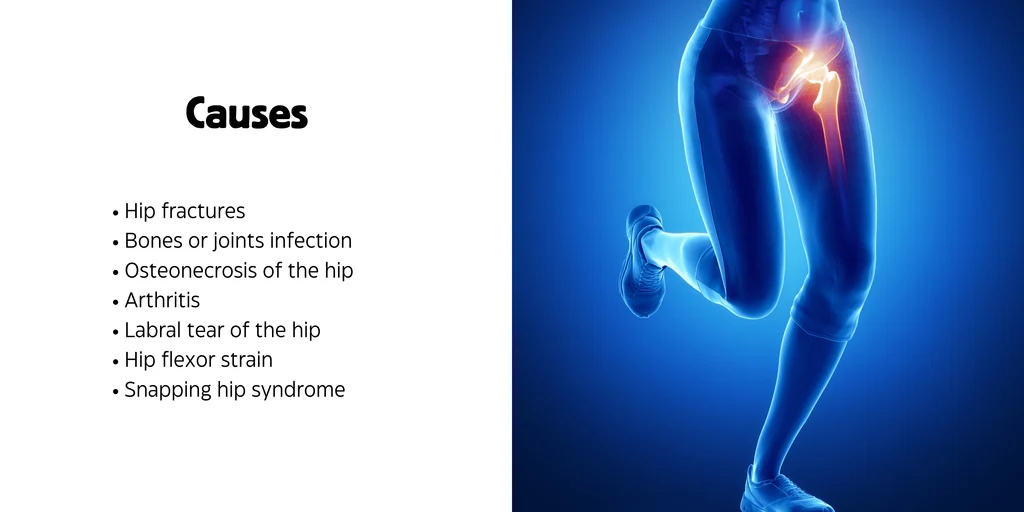

علت صدا دادن مفصل ران و لگن

دلایل دیگر صدا دادن مفصل لگن

علاوه بر سندروم اسنپینگ، عوامل دیگری هم در ایجاد این صداها نقش دارند: